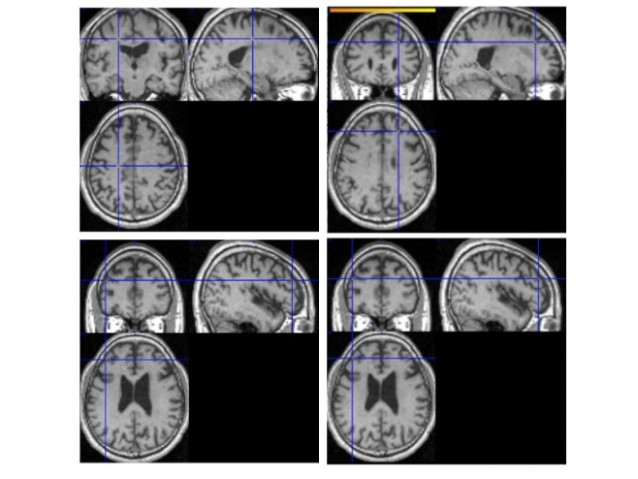

In our preliminary investigations, we were able to achieve classification of fMRI data of depressed and healthy subjects with 82.6% accuracy using a binary classification algorithm referred to as LASSO (least absolute shrinkage and selection operator). Figure 1 shows the location of the weights in the brain, which were found to contribute to the identification of depressed subjects (positive weights) and that which were found to contribute to the distinction of healthy subjects (negative weights). These results build the basis for adding further biomedical parameters such as brain volume, serotonin level etc to our classification.

Figure 1: (Upper row) locations that positively contribute to the identification of depressed subject. (Bottom row) locations that are typically activated in healthy subjects.